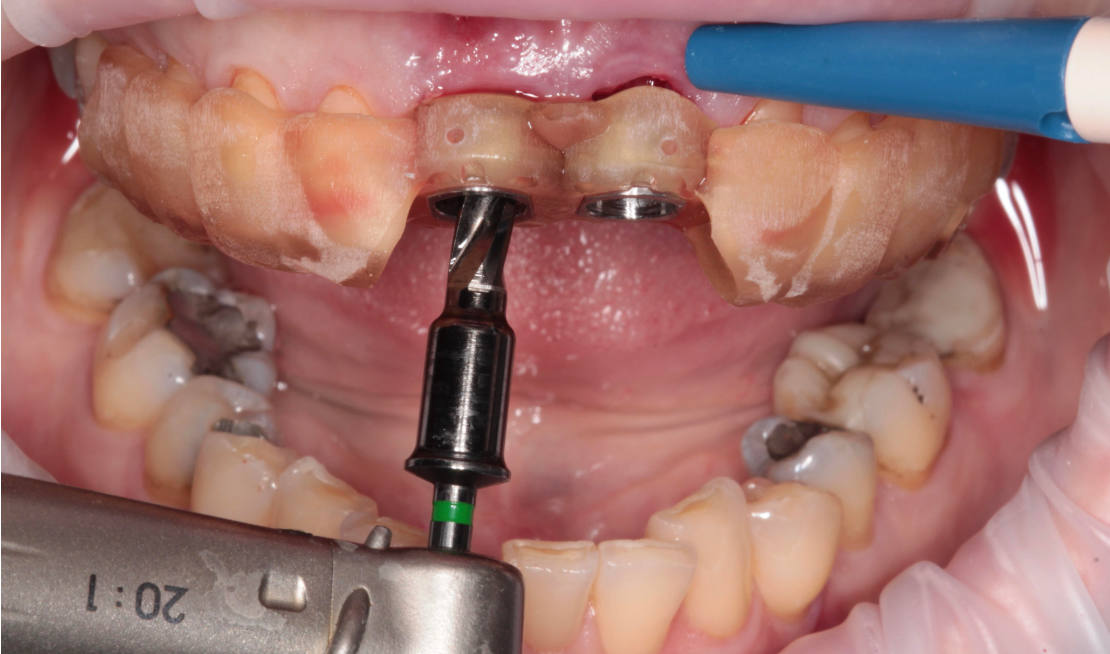

Jediným riešením bola extrakcia obidvoch zubov. Najväčšou obavou zo strany pacientky bola strata obidvoch predných zubov a následného fungovania bez nich pri práci s ľuďmi. Ideálnym riešením teda bola náhrada zubov implantátmi spolu s nasadením koruniek, a to počas jedného sedenia. V deň konzultácie bol pacientke urobený sken pomocou intraorálneho skeneru 3Shape TRIOS, ktorý nám umožňuje zobraziť 3D simuláciu ústnej dutiny. Pomocou softwaru 3Shape Implant Studio sme spojili dáta z intraorálneho skenu a CBCT, STL a DICOM súbory. V ďalšom kroku sme virtuálne vložili implantáty v správnej protetickej polohe, navrhli šablónu pre ich zavedenie, namodelovali individuálne abutmenty a korunky (obr. 4). Kompletné dáta sme exportovali pre frézovanie a 3D tlač. V laboratóriu sa pomocou 3D tlačiarne vytlačila chirurgická šablóna, ktorá nám slúži na presné zavedenie implantátov – použili sme implantačný systém Dentium Super Line. Následne boli vyfrézované zirkonové abutmenty a plastové dočasné korunky(obr. 5).

Následne sme použili protokol vŕtania a zavedenia implantátov cez šablónu (obr. 7, 8), na ktorej sme mali orientačné body pre správne napolohovanie implantátov, abutmentov a koruniek (obr. 9–14).